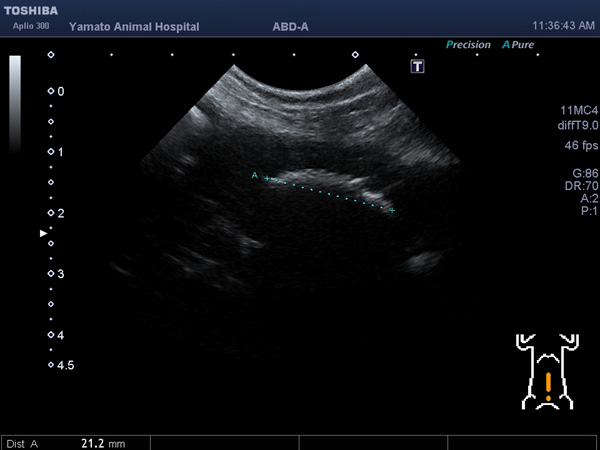

血尿、頻尿の症状で来院されました。レントゲン・超音波検査にて、膀胱内に結石を認め、手術による摘出となりました。無事手術も終わり元気に退院しました。よかったね。